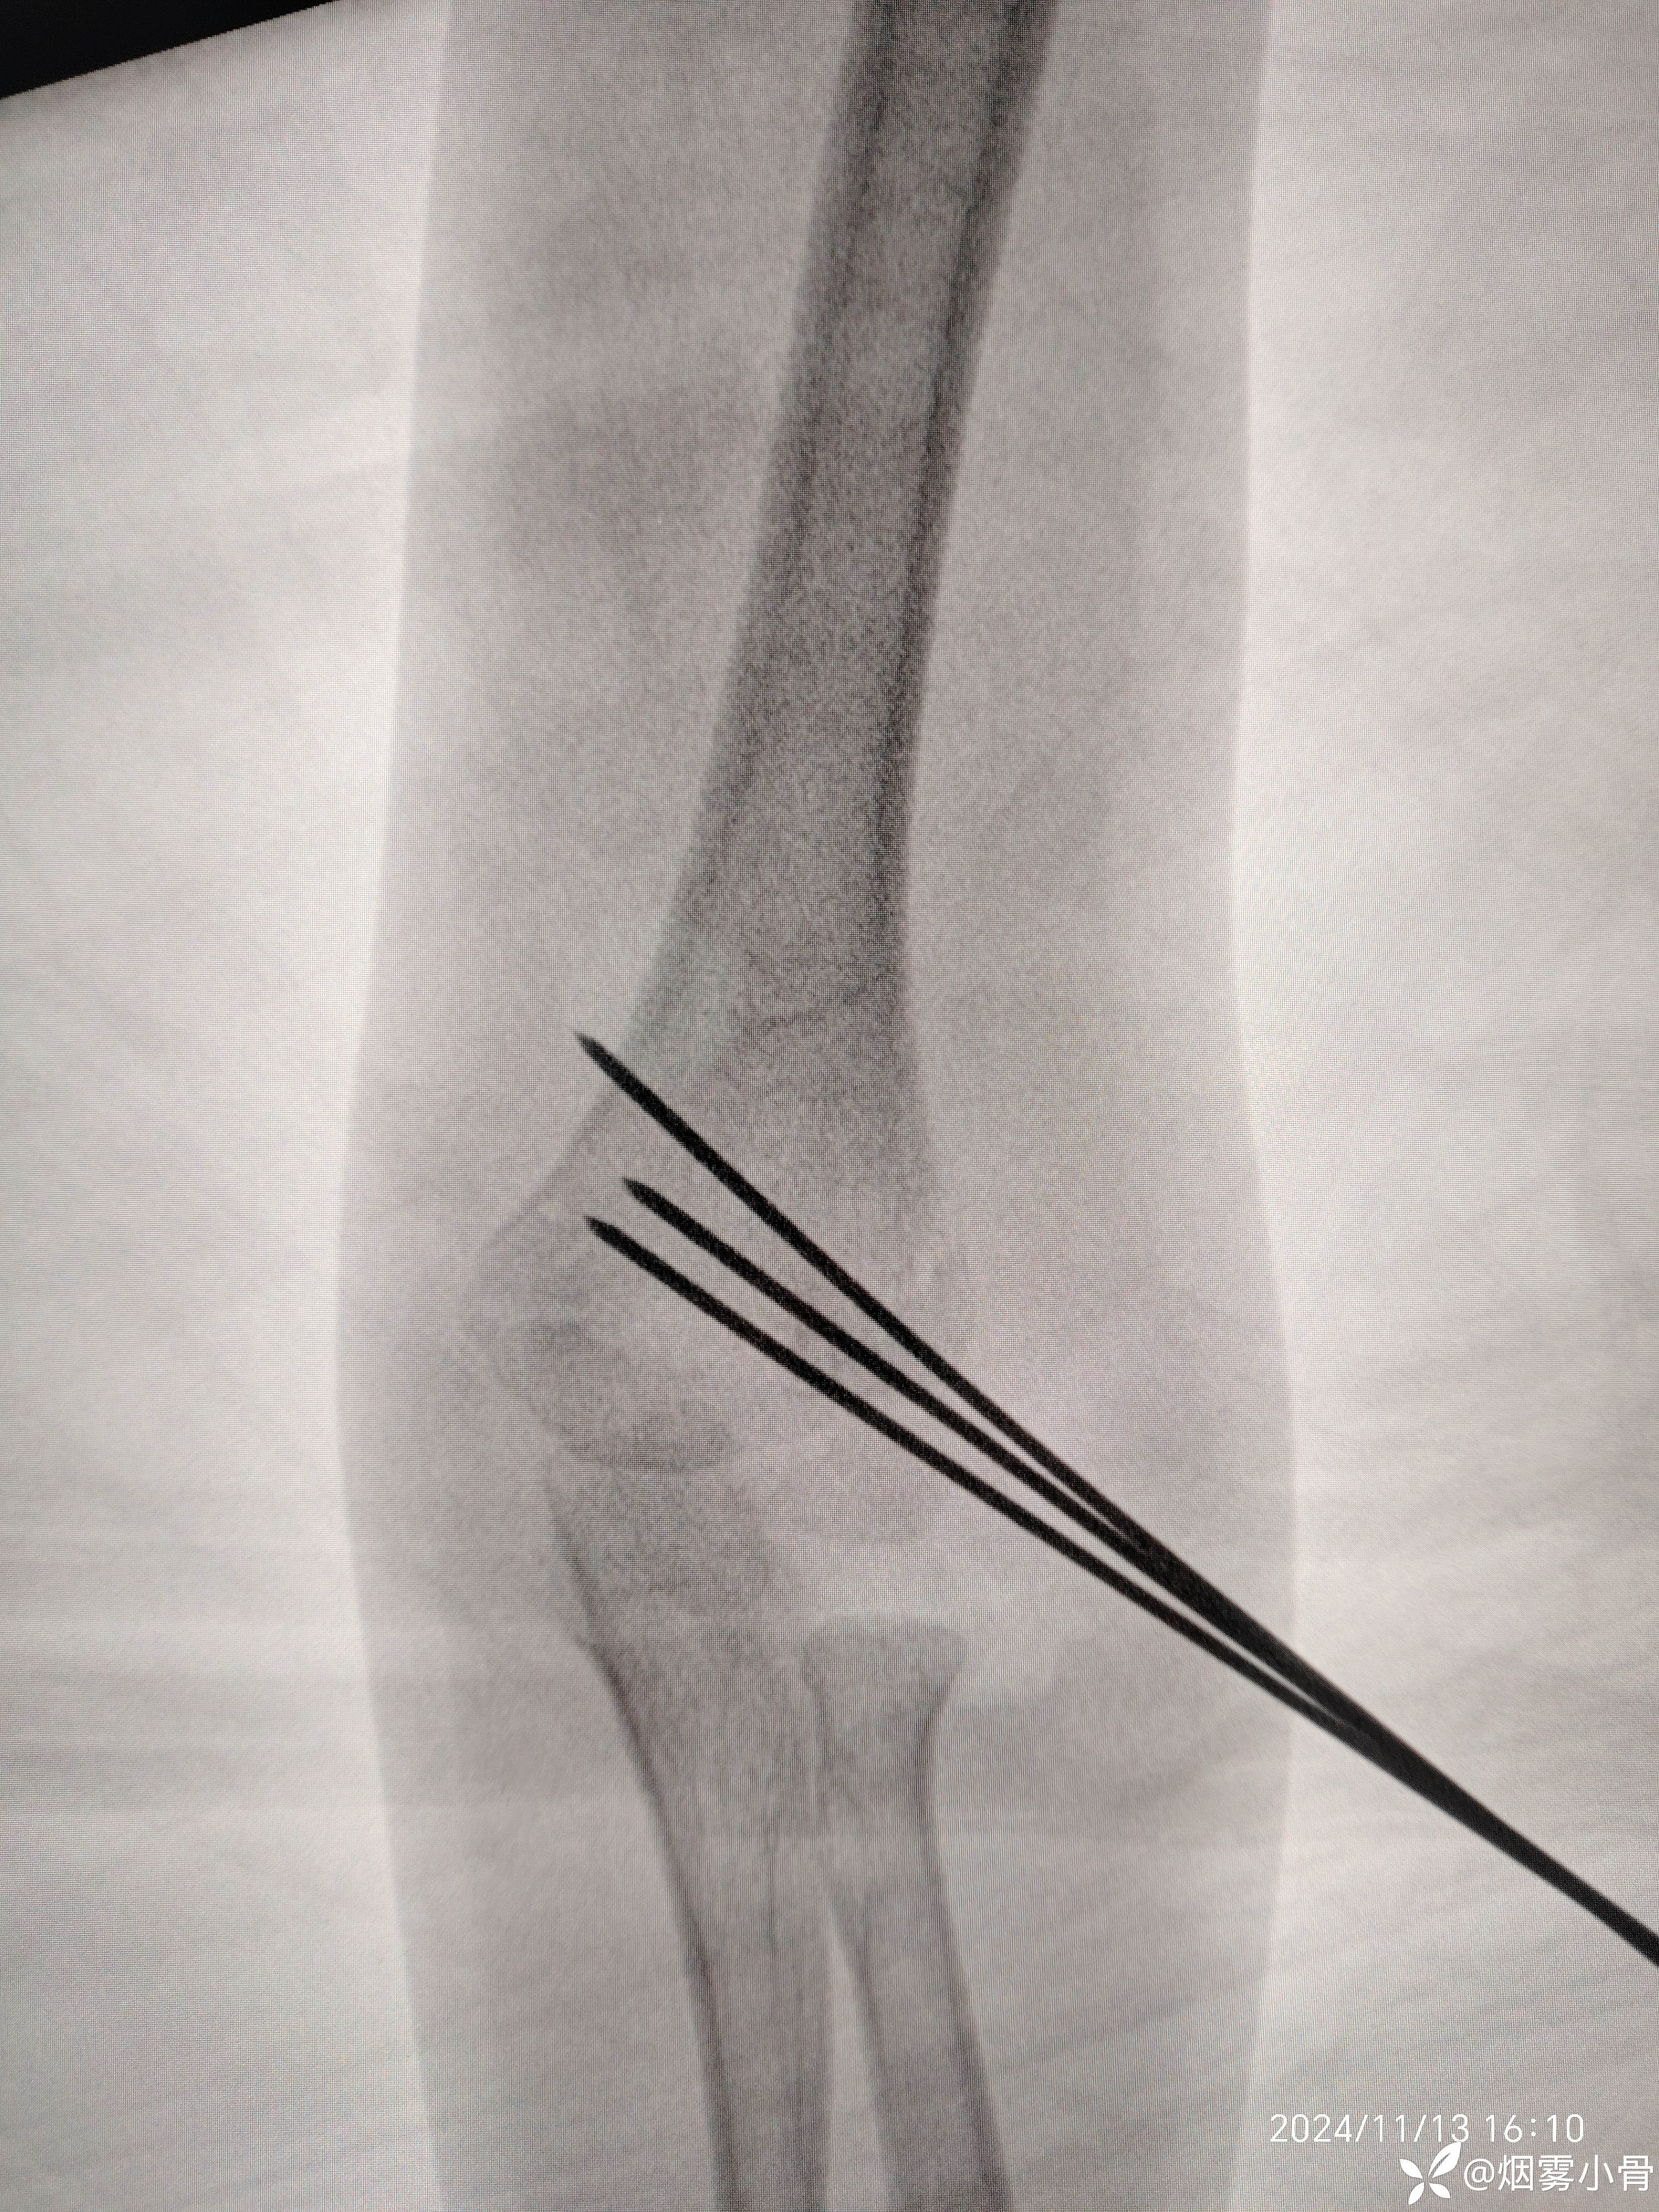

6岁肱骨髁上骨折,急诊30分钟完成零切开闭合复位克氏针内固定

【治疗经过及结果】:

30分钟完成一例肱骨髁上骨折闭合穿针及石膏固定手术,术中透视拍片8张。